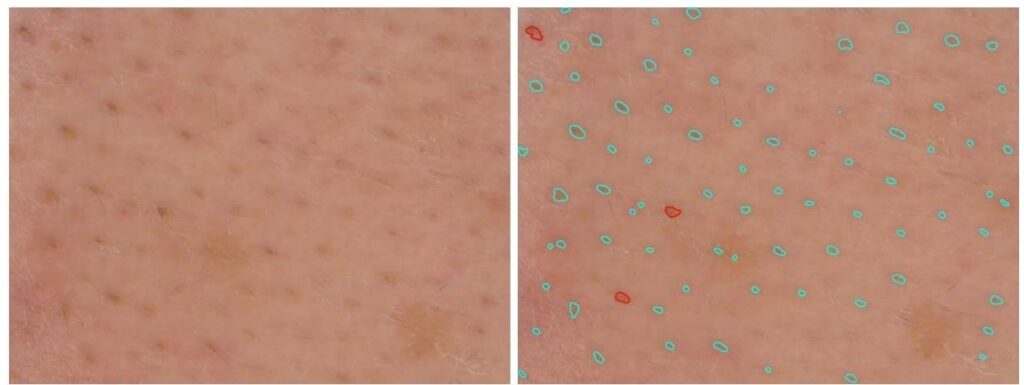

Excessive sebum production can affect pore size. These can expand. Thanks to its reliable dimensional measurements and metric calibration, the C-Cube can detect the number of pores and measure them in 2D and 3D.

In 2D, this involves color analysis, followed by shape identification to eliminate other objects and retain only the pores. The results are images processed in black and white. You also get a spreadsheet with the median area, median diameter and pore density of each image.

3D analysis provides an additional dimension of pore depth. The 3D approach improves the sensitivity of pore detection. It can then be used to assess the depth of the pores and their possible filling.

Source image Processed image